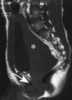

T2-hypointense prostate mass